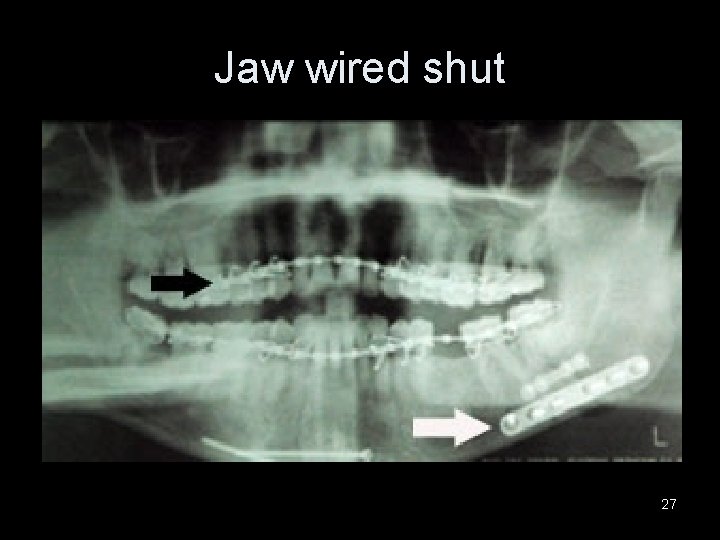

Jaw wired shut 27